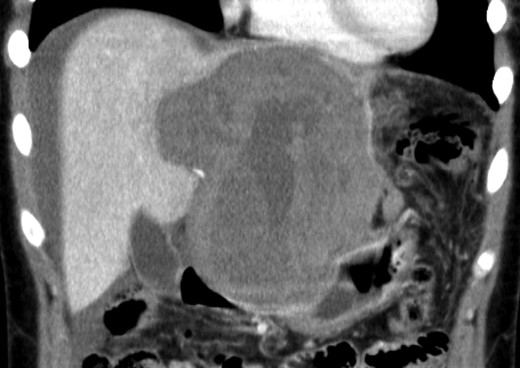

An 18-year-old woman presented with epigastric pain that started during a Japanese drum lesson. She was diagnosed with rupture of a hepatic tumor and transported to our hospital. She had no medical history of surgery, including abdominal surgery. Contrast-enhanced computed tomography (CT) revealed a 13-cm, low-density giant mass in the left hepatic lobe and high-density ascites, indicating abdominal bleeding from the liver tumor (Fig. 1). Ultrasonography confirmed a well-defined giant mass of the liver, comprising both cystic and solid lesions. Laboratory data showed a low hemoglobin level of 8.2 g/dl, and all the results of liver function tests and tumor marker measurement were within normal ranges. The patient underwent emergent celiac angiography, which revealed an avascular tumor with no evidence of extravasation from the hepatic artery. The left hepatic artery was considered to be the artery feeding the tumor and was embolized (Fig. 2). Magnetic resonance imaging (MRI) confirmed a well-defined giant multilocular lesion with fibrous partition (Fig. 3). After the patient's condition stabilized, she underwent left hepatic lobectomy. Laparotomy revealed bloody ascites and a large tumor in the left lobe of the liver; the right lobe appeared normal. The enlarged lymph nodes of the hepatoduodenal ligament were also dissected. Histological analysis of the resected specimen revealed a huge cystic mass of ∼12 × 9.5 cm. The mass was cystic and multilocular with a fibrous wall and filled with a massive blood clot (Fig. 4). The enlarged lymph node had a 25 × 23-mm cyst, which contained yellowish fluid. On microscopic examination, the wall of the cyst consisted of a tight elastic fiber meshwork composed of collagen fibers, which was accompanied by a small amount of acid mucopolysaccharide in the stroma and a lining of single-layered flat cells on the inner wall (Fig. 5a and b). Immunohistochemical staining revealed that the cyst wall was positive for both the endothelial marker CD31 and the lymphangial marker D2-40 (Fig. 5c and d). The cystic structure of the lymph node also was composed of elastic fiber components similar to those of the cyst in the liver and lined with single-layered flat cells, which were immunohistochemically positive both for CD31 and D2-40 (Fig. 5e). The pathological diagnosis was hepatic lymphangioma combined with lymphangioma of the lymph nodes. The patient's postoperative course was uneventful, and she was discharged on Day 8. During follow-up for almost 4 years since the surgical treatment, the patient has presented no sign of recurrence.

Enhanced CT scan demonstrated a low-density giant mass 13 cm in size and high-density ascites.